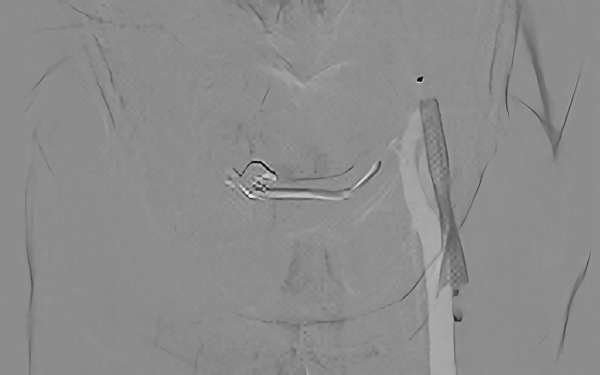

症例 '19年7月

No.

581

'19年7月26日

左内頚動脈狭窄症

70代

院内外来

手術写真

中